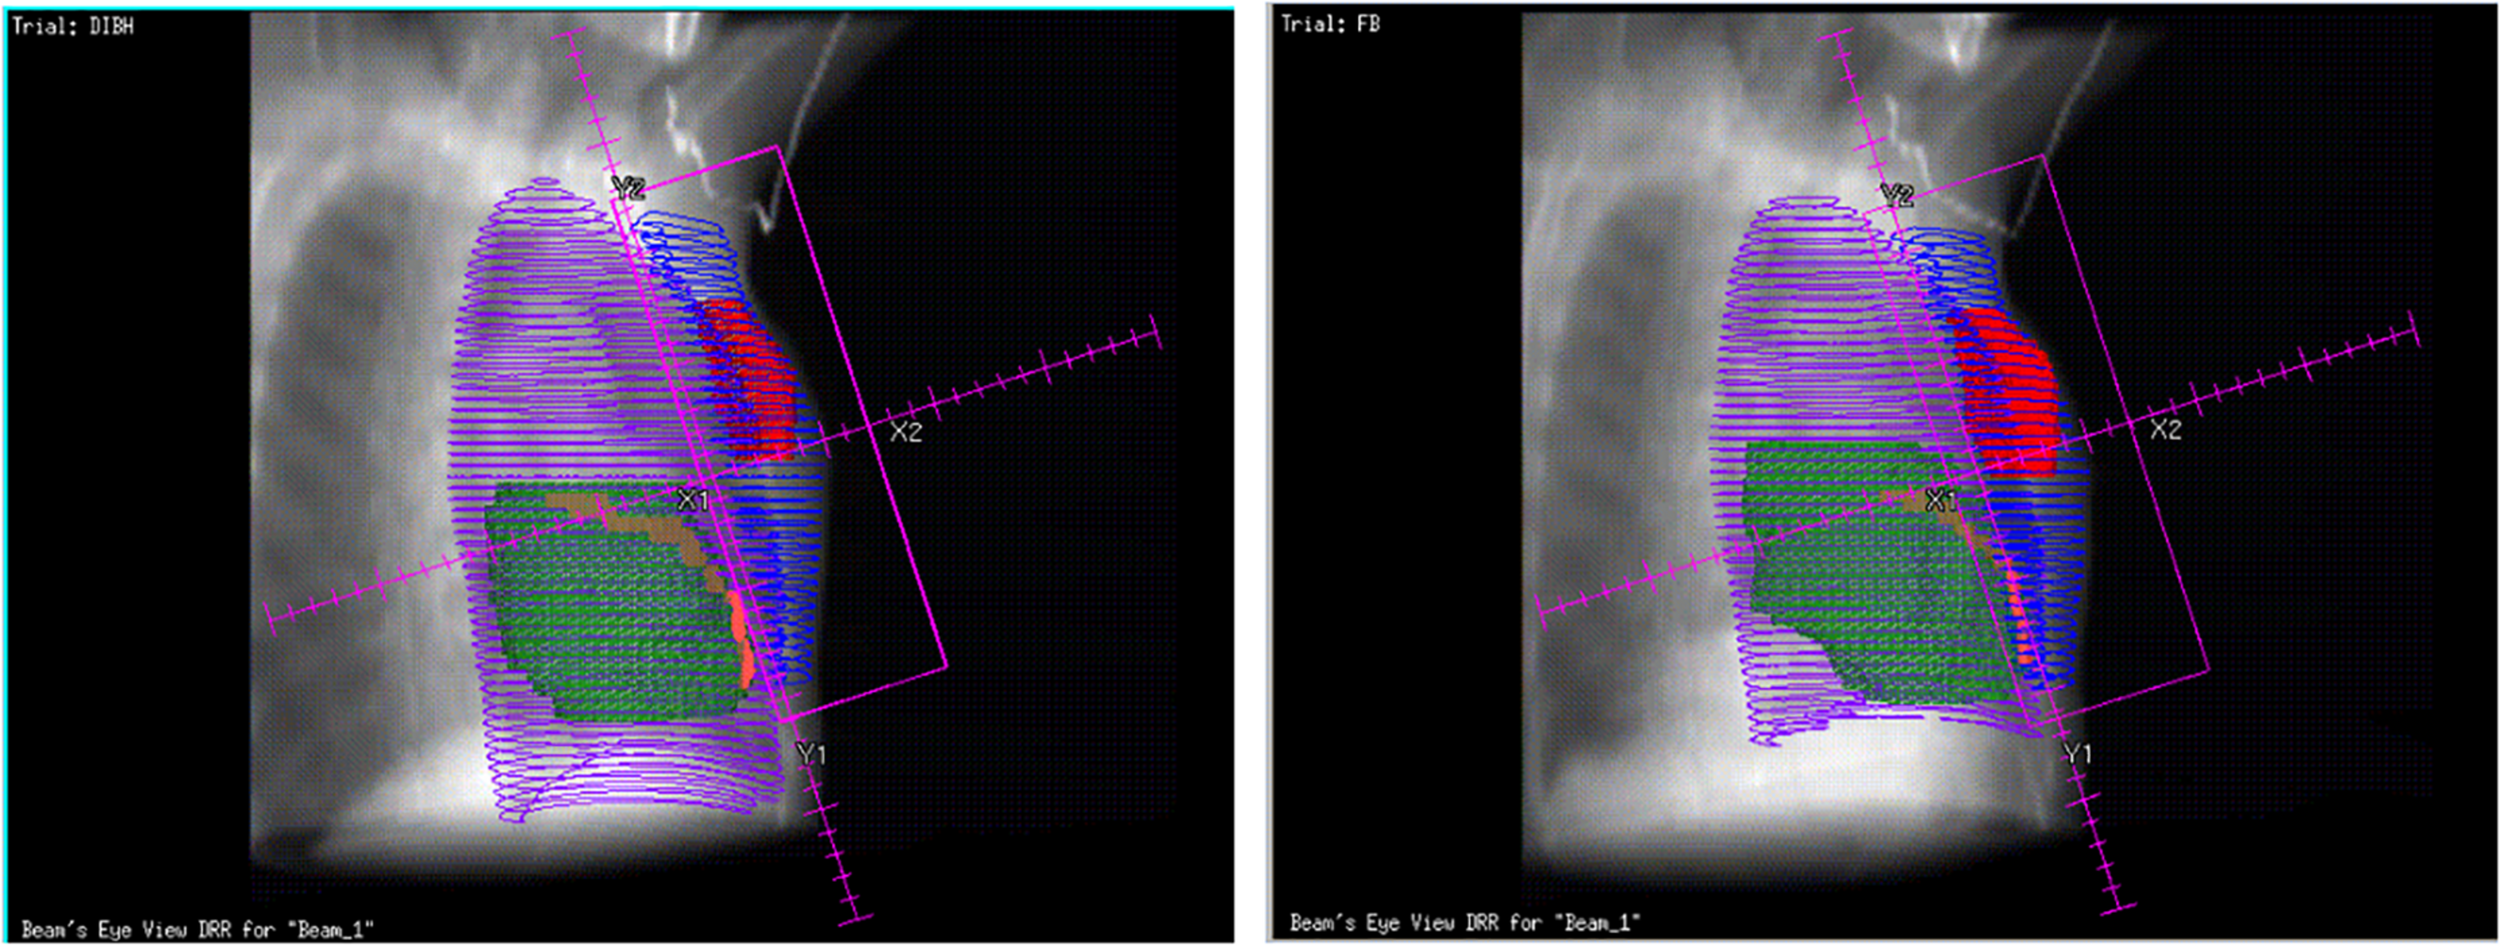

The DVH parameters are all listed in Table 2 and shown in Figure 2, which illustrate a significantly reduced dose to the heart and LAD coronary artery in the DIBH plan. For demonstration purposes, with the same patient, we show the dose distribution and a beam’s view from the medial tangential field for the DIBH and FB plans in Figure 5. Furthermore, no significant differences were found in homogeneity, with a mean HI of 0.278 ± 0.038 for the DIBH plan compared with 0.293 ± 0.052 for the FB plan.

FIGURE 5

Bean’s eye views of the medial tangential field during DIBH (left) and FB (right) for a typical patient. During inspiration the lung volume (purple line) is increased, the breast (blue line) is moved cranioventrally and the heart (green) caudally In the shown case, the heart and LAD coronary artery (orange) were not included in the beam portal during DIBH.